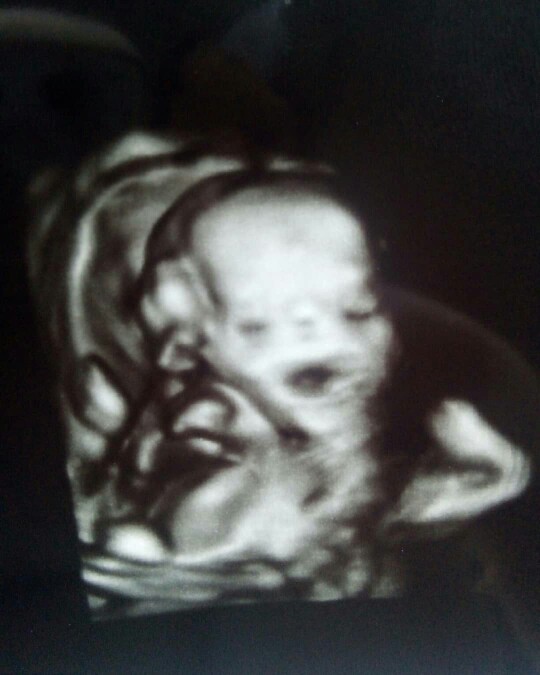

รูปนี้ตอน 15 สัปดาห์

ชัดเจนเลยค่ะ